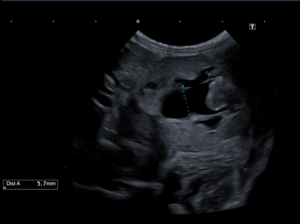

- エコー検査: 著しい尿管の拡張と腎盂の拡張。尿管径は5.7mmと、通常(1mm以下)より大きく拡張していました。

尿管結石による不完全閉塞と診断し、これは腎臓から出た尿の排泄経路の問題(腎後性)による急性腎障害(AKI)でした。